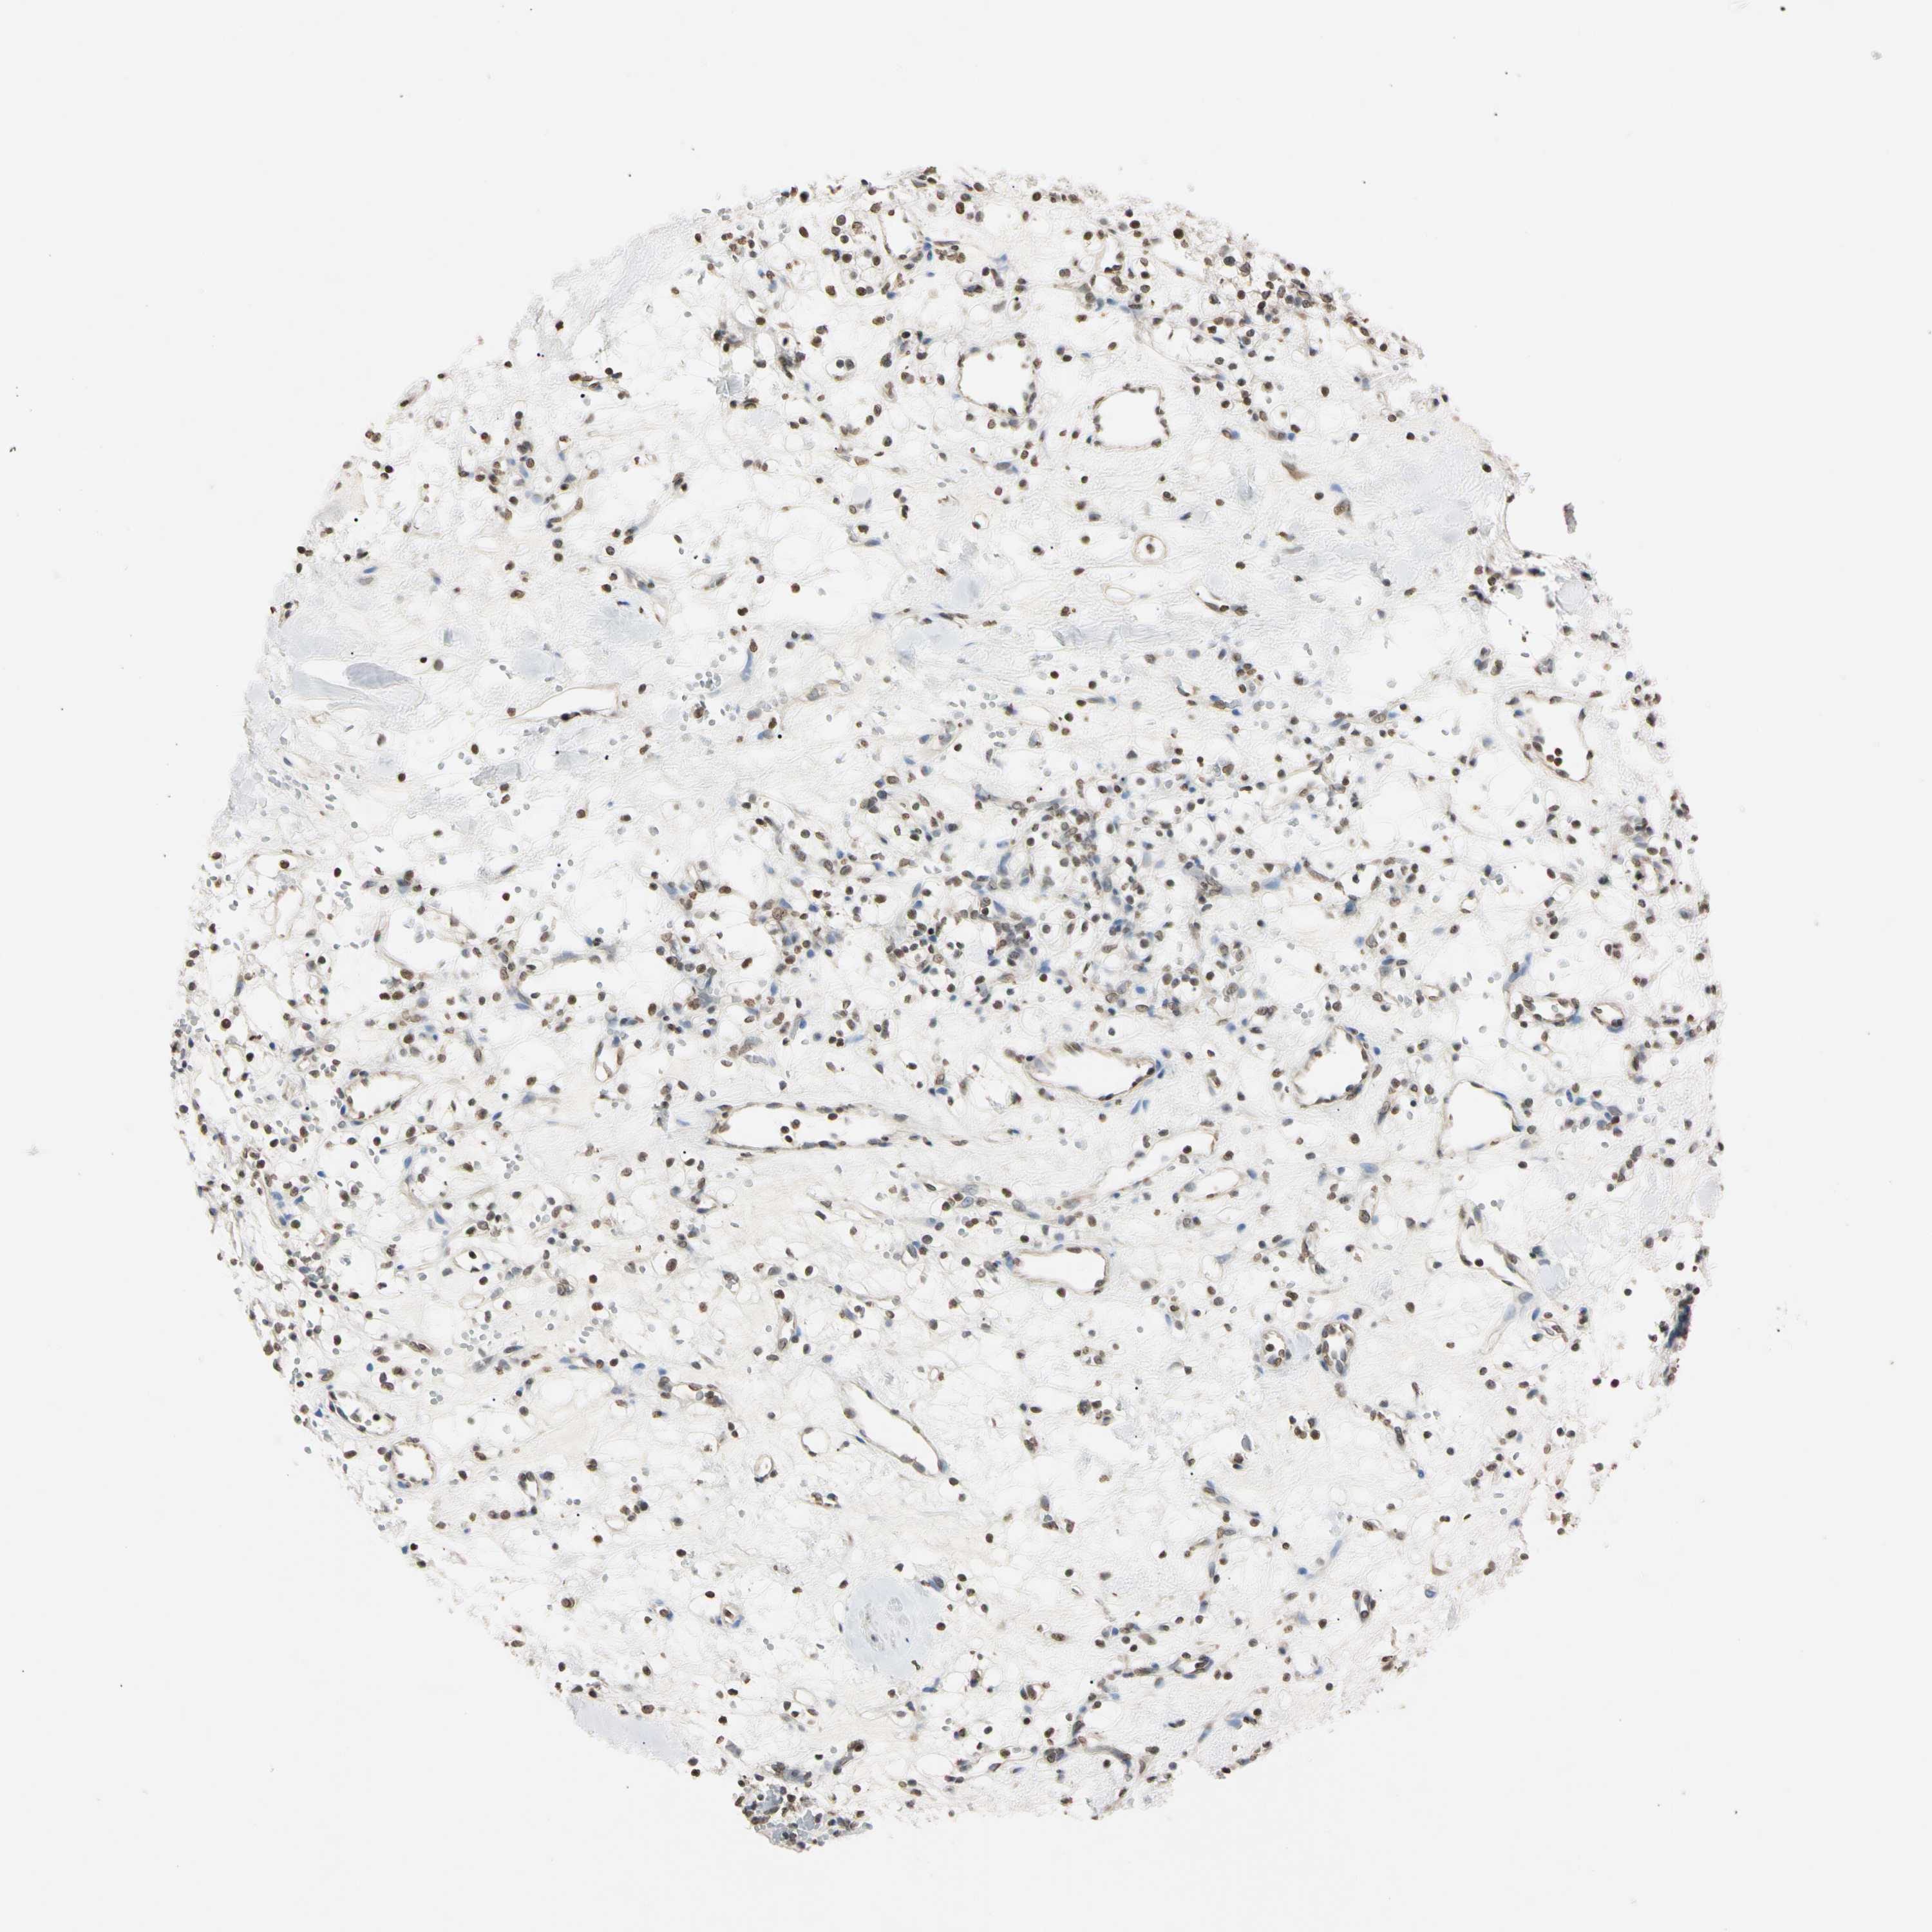

KIDNEY RENAL PAPILLARY CELL CARCINOMA (TCGA) - Interactive survival scatter ploti

The Survival Scatter plot shows the clinical status (i.e. dead or alive) for all individuals in the patient cohort, based on the same data that underlies the corresponding Kaplan-Meier plots. Patients that are alive at last time for follow-up are shown in blue and patients who have died during the study are shown in red.

The x-axis shows the expression levels (FPKM) of the investigated gene in the tumor tissue at the time of diagnosis. The y-axis shows the follow-up time after diagnosis (years). Both axes are complimented with kernel density curves demonstrating the data density over the axes. The top density plot shows the expression levels (FPKM) distribution among dead (red) and alive patients (blue). The right density plot shows the data density of the survived years of dead patients with high and low expression levels respectively, stratified using the cutoff indicated by the vertical dashed line through the Survival Scatter plot. This cutoff is automatically defined based on the FPKM cutoff that minimizes the p-score. The cutoff can be changed by dragging the vertical line or by entering a cutoff value in the square labeled "Current cut-off".

Under the Survival Scatter plot the p-score landscape (black curve; left axis) is shown together with dead median separation (red curve; right axis). Dead median separation is the difference in median mRNA expression between patients who have died with high and low expression, respectively. It is calculated as follows: median FPKM expression of dead patients with high expression - median FPKM expression of dead patients with low expression. This is intended to aid the user in visually exploring custom cutoffs and the associated p-scores and dead median separation.

Individual patient data is displayed and can be filtered by clicking on one or more of the category buttons on the top of the page. Categories describing expression level and patient information include: high, low, alive, dead, female, male and tumor stages. The scale of the x-axis can be toggled between linear and log-scale by clicking on the "x log" button. Mouse-over function shows TCGA ID, patient information and mRNA expression (FPKM) for each patient.

& Survival analysisi

Kaplan-Meier plots summarize results from analysis of correlation between mRNA expression level and patient survival. Patients were divided based on level of expression into one of the two groups "low" (under cut off) or "high" (over cut off). X-axis shows time for survival (years) and y-axis shows the probability of survival, where 1.0 corresponds to 100 percent.

CDC45 is potential prognostic, high expression is unfavorable in Kidney Renal Papillary Cell Carcinoma (TCGA)